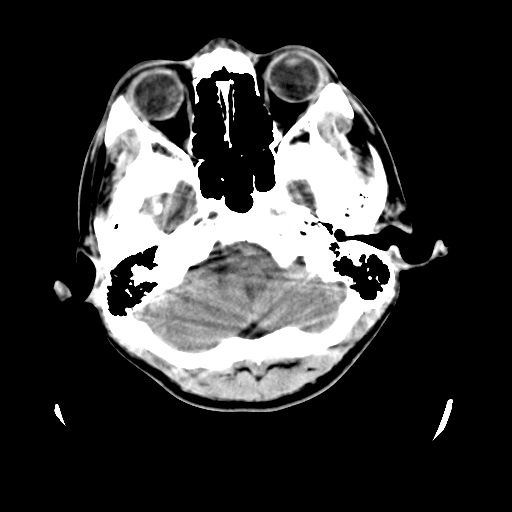

标题: CT23601:男, 17岁,剧烈头痛一小时。 [打印本页]

标题: CT23601:男, 17岁,剧烈头痛一小时。

男, 17岁,剧烈头痛一小时。